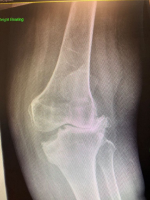

With more than 1,000 knee and hip replacements performed, Mr Mughal has extensive experience across all aspects of knee surgery. He has developed one of the largest specialist practices in the West Midlands for kneecap instability and has significant expertise in treating sports related knee injuries. His research includes publishing one of the world's largest series combining alignment and ligament surgery for recurrent kneecap dislocation, as well as widely adopted techniques for patellar realignment.

Mr Mughal is also highly experienced in deformity correction for both adolescents and adults, including knock knee, bow leg deformities and the complex condition known as miserable malalignment syndrome. He uses advanced computer based and 3D modelling techniques to plan personalised corrective surgery, aiming to preserve joints affected by early osteoarthritis. When combined with cartilage regeneration procedures, this approach enables him to offer a comprehensive and tailored treatment pathway.